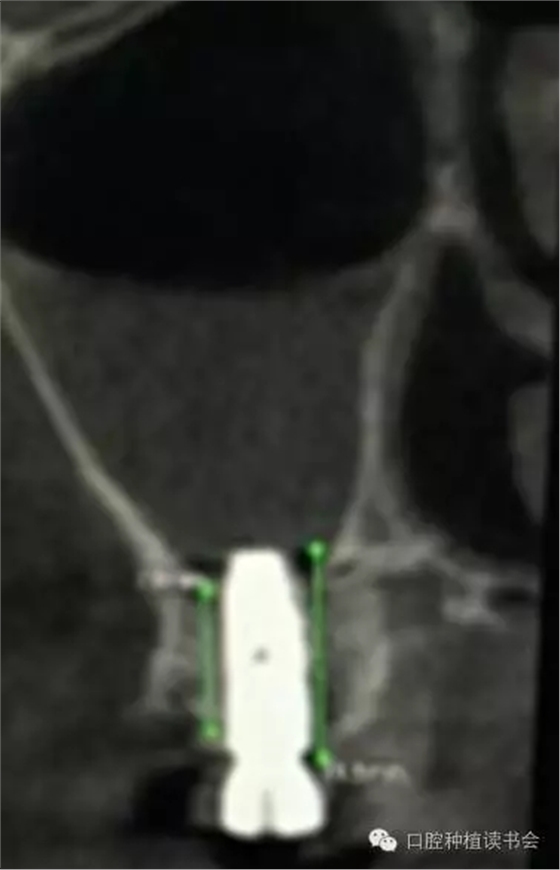

支配上頜竇的動(dòng)脈有上牙槽后動(dòng)脈(PSAA)、眶下動(dòng)脈和鼻后外側(cè)動(dòng)脈,手術(shù)時(shí)應(yīng)避免損傷。CBCT矢狀面可以觀察到上頜竇前外壁和后外壁的血管影像,PSAA從后外壁進(jìn)入上頜竇內(nèi),在冠狀面上則表現(xiàn)為位于骨壁外、骨壁內(nèi)或貫穿骨壁的血管影像(圖6-7)。

PSAA與眶下動(dòng)脈吻合,分布在上頜竇粘膜,常位于骨壁內(nèi)或貫穿骨壁。尸檢報(bào)告顯示,動(dòng)脈最低點(diǎn)距牙槽脊頂?shù)拇怪备叨染禐?1.25+2.99mm,距上頜竇底約8mm(Solar,1999)。因此,上頜竇提升時(shí),即使是非開(kāi)窗的牙槽脊頂入路,也有出血的風(fēng)險(xiǎn)(圖8-9)。